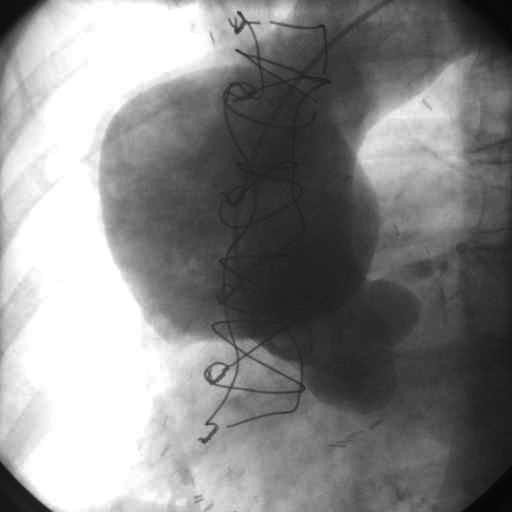

Arterioqrafiya – mənfəzdaxili stenozun yerinin, dərəcəsinin qiymətləndirilməyə və trombotik xəstəliyi embolik xəstəlikdən differensiasiya etməyə imkan verir. Lakin təcili vəziyyətlərdə istifadəsi əlverişli deyil.

Embolektomiya – birbaşa (embolun üzərindən kəsik edib, onun mexaniki olaraq xaric edilməsi) və dolayı yolla (distal və yaxud proksimal olaraq – bazu və ya bud arteriyası üzərindən arteriotomiya edib, xüsusi Foqarti kateteri ilə embolektomiya) icra edilə bilər. Proses əksərən lokal anesteziya altında icra edilir. Embolektomiya zamanı gətirici və aparıcı damarların keciriciliyinin tam bərpası təmin edilməlidir. Punksiya olan yerdən gətirici, aparıcı arteriyalar əldə edildikdən və embolektomiyadan sonra arteriotomik kəsiyə 6/0 prolen sapla tikiş qoymaq lazımdır. Göstərişlər olduqda embolektomiya angioqrafiya ilə yekunlaşdırıla bilər. Stenoz olan nahiyədə in situ kəskin tromboz yarandıqda proseduranı rekonsrtruktiv əməliyyatla (şunt qoymaqla) tamamlamaq tövsiyyə edilir.

Perkutan Transluminal Koronar Angioplastika (PTKA) – bəzi arteriostenozların revaskuyarizasiyası üçün istifadə edilir. Tam tıxanmalarda lazer köməyi ilə maneənin üzərində balonun keçə biləcəyi dəlik açılır. Lakin böyük manələrdə əksərən restenoz müşahidə edilir.

Əsas müayinələr: Exokardioqrafiya, 24 saatlıq monitorinq, angioqrafiya.

Endovaskulyar əməliyyatlar sərbəst və yaxud damarlar üzərində aparılan cərrahi əməliyyatlarla birlikdə icra edilə bilər. Son vaxtlar daha çox yayılmış metod kimi medikamentoz regionar trombolizisə böyük əhəmiyyət verilməkdədir. Əgər trombolizisdən sonra arteriyada stenoz aşkar edilərsə, bu halda prosedura damarın angioplastikası və göstəriş olduqda stentlənməsi ilə sona çatdırılmalıdır. Yeni metodlardan sayılan transkutan aspirasion və mexaniki trombektomiya cərrahi müalicəyə alternativ hesab edilir və medikamentoz trombolizislə kombinasiyada trombun tez sorulmasında və son nəticədə kəskin işemik dəyişikliklərin qarşısının alınmasında həlledici rol oynayır.